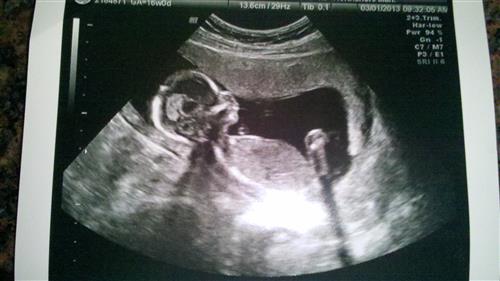

16 weeks